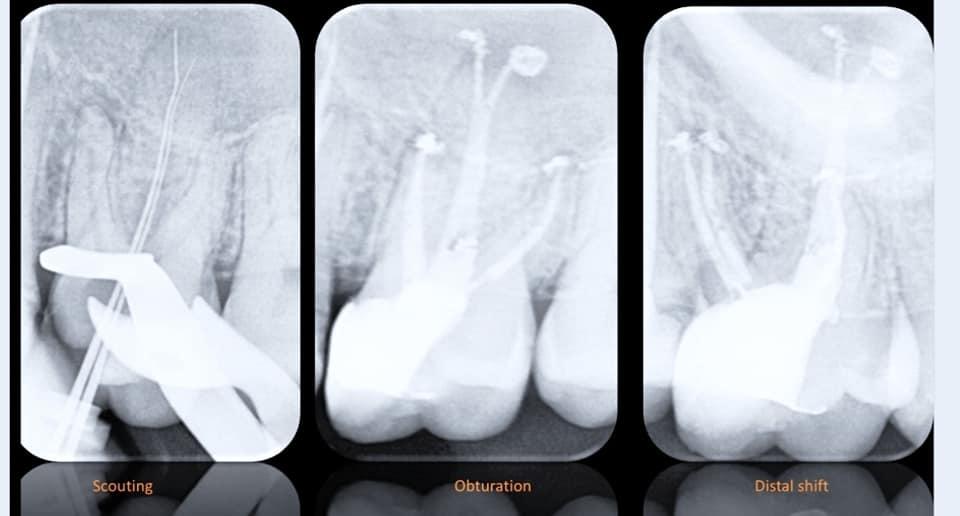

AF ROTARY

一位47岁的女性牙齿严重钝痛。有根管治疗史。9个月后牙齿开始出现反应,去除旧的填充物后的首要目标是确保牙齿的可修复性。使用Thermacut钻进行牙龈切除术。根管严重钙化,很难获得通畅。使用Fanta C锉探查,使用Fanta ROTARY#25锥度0.04预备根管,最终#30锥度0.04的锉完成预备。 用EDDY超声探头荡洗并用EDTA 17%和NaOCl 3%冲洗。 使用WVC和BCS进行封闭。使用Tetric EvoCeram进行最终修复。

来自Dr. Ahmed Alwaidh